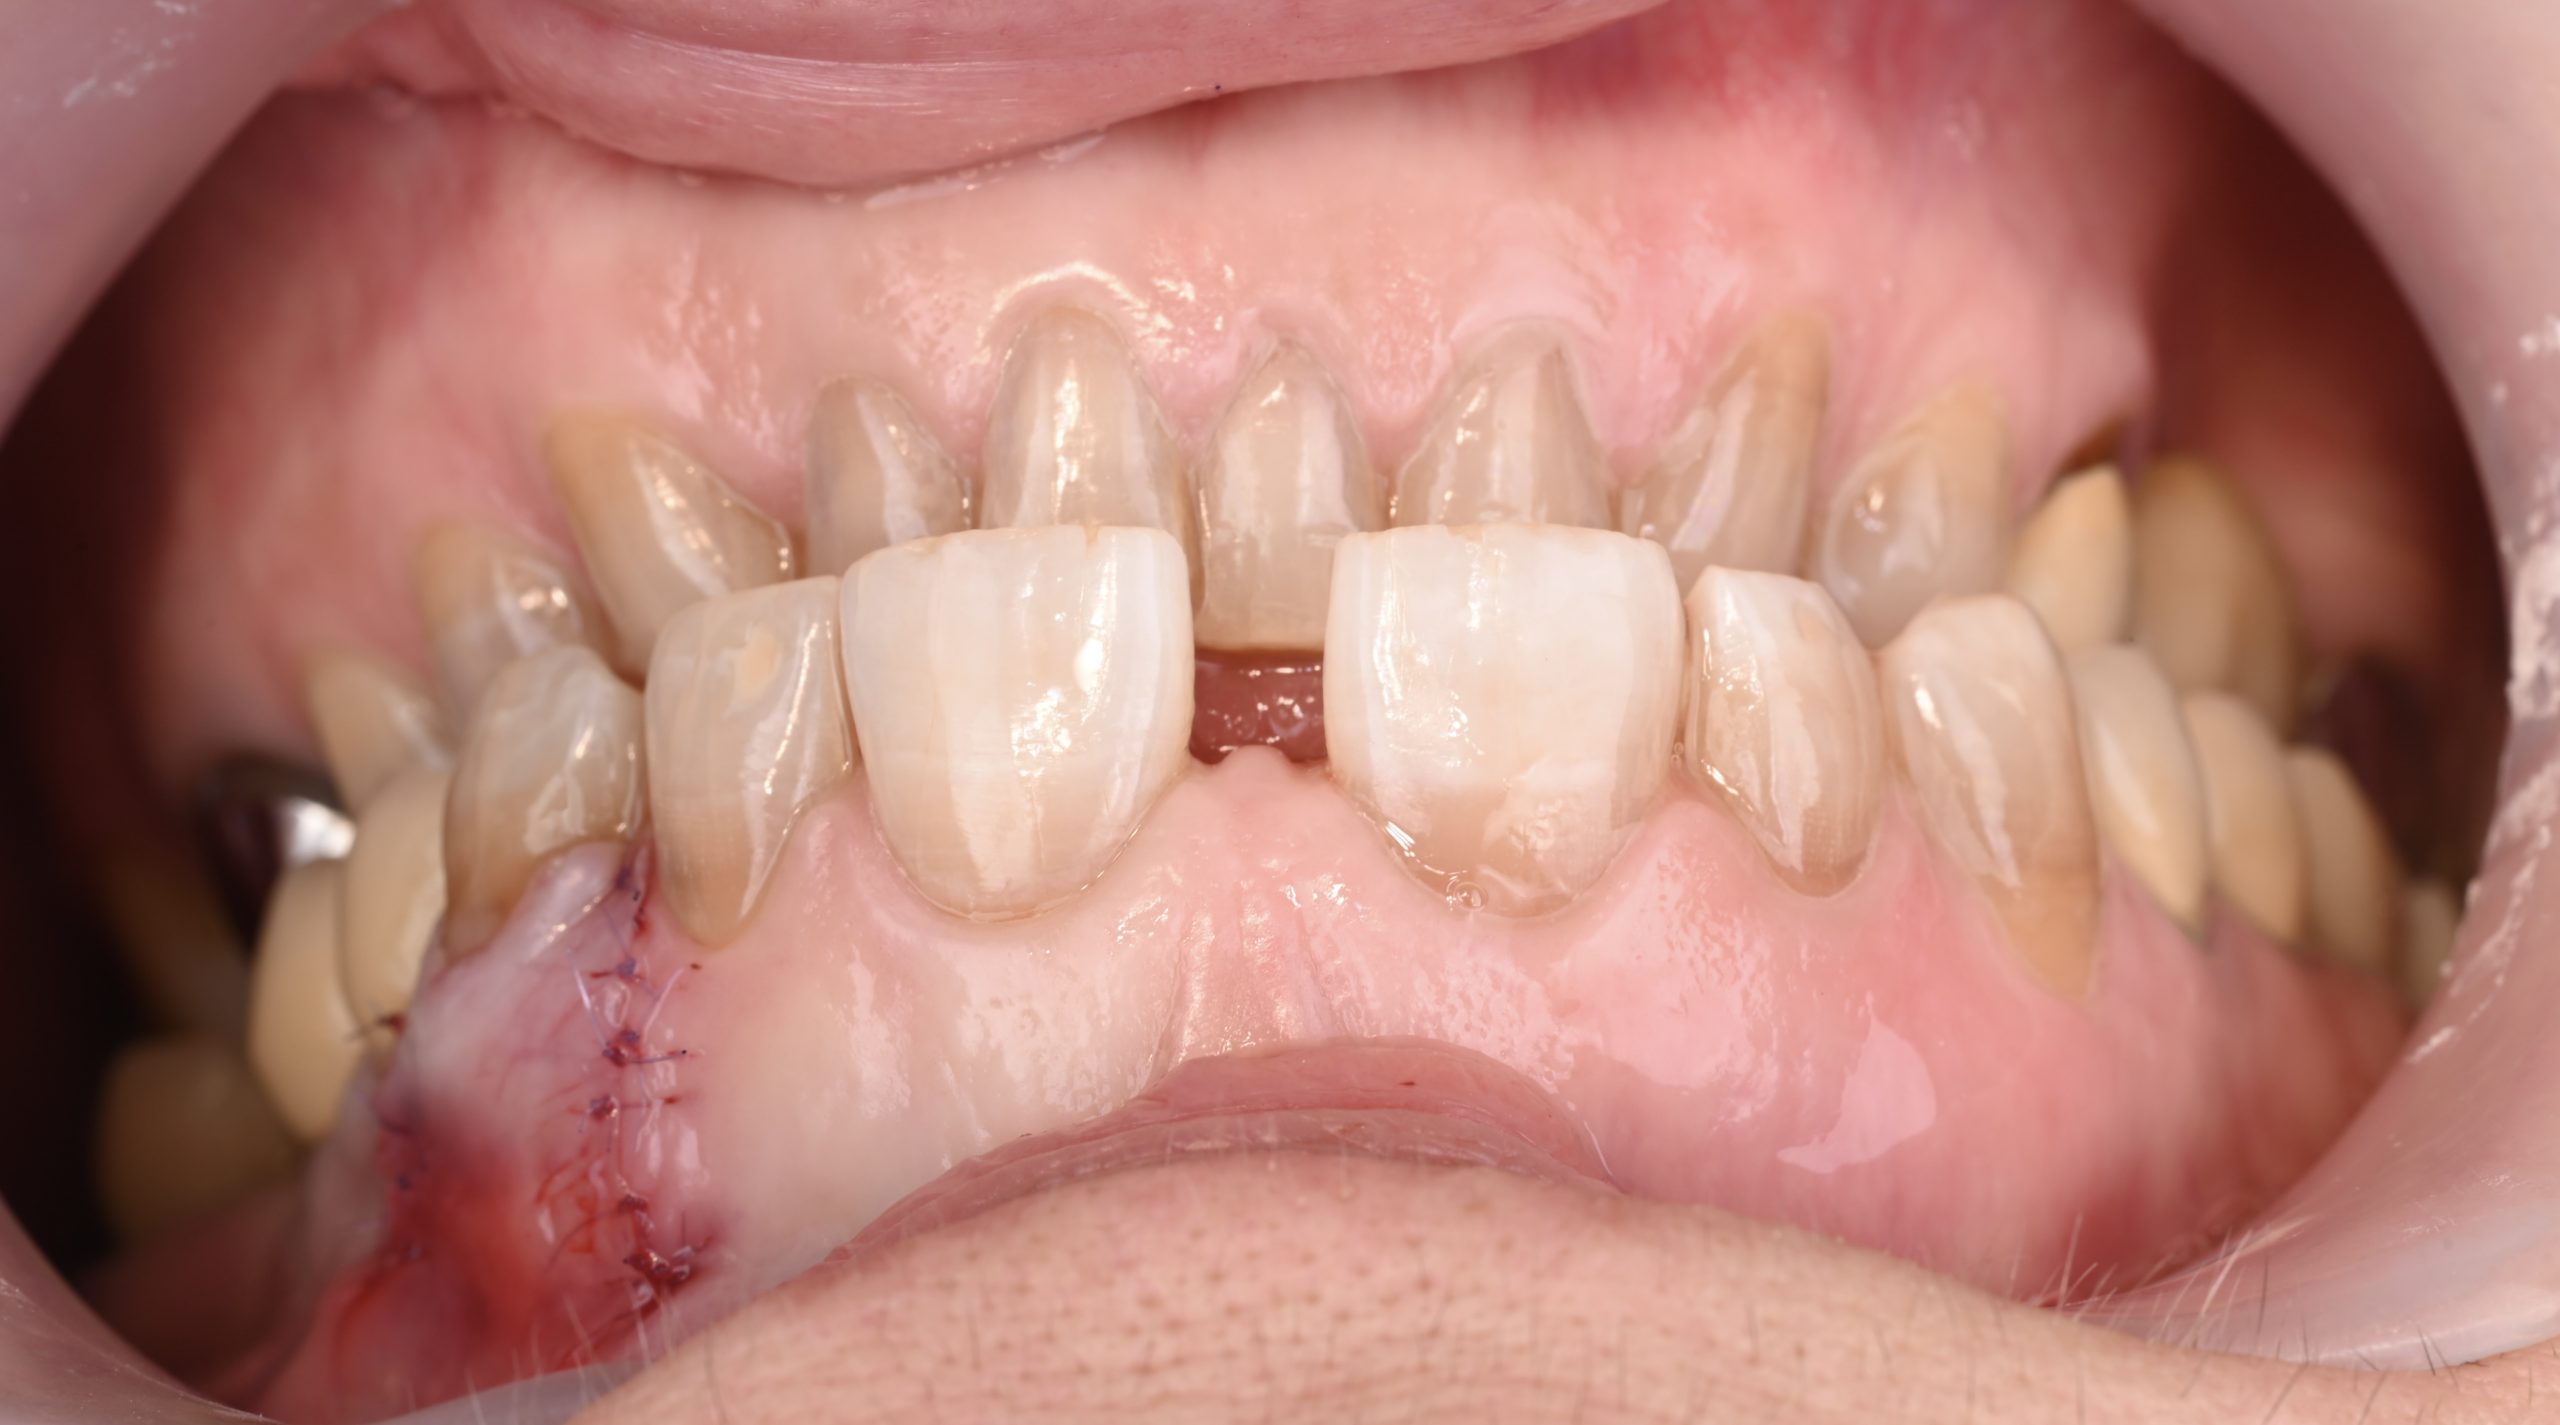

Avant

Before